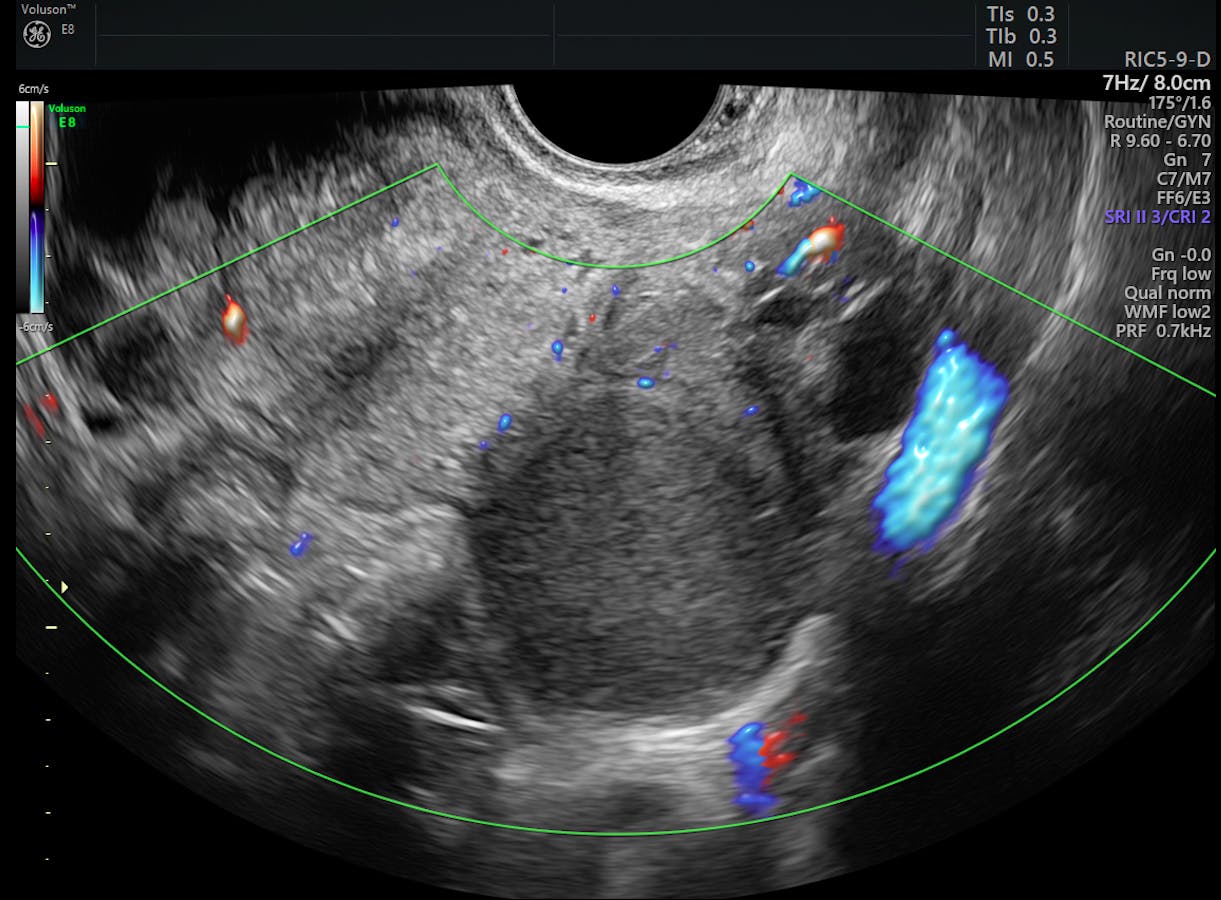

Can mris and ultrasounds detect endometriosis? What can the ultrasound diagnose? Learn about endometriosis, including possible treatments for this condition that causes pain and sometimes infertility. Transvaginal ultrasound allows an accurate assessment of the vagina, particularly the areas of the although the sensitivity and specificity of tvs in the prediction of deeply infiltrating endometriosis. It manifests in three ways; 1.3.4 3d sonography in the diagnosis of rectovaginal endometriosis. Ultrasound is an effective tool to detect and characterize endometriosis lesions. Endometriosis is more common in women who are having fertility issues, but it does not necessarily cause infertility.

Ultrasound could be more useful in identifying pelvic de compared with mri, but none of the the disadvantage of ultrasound in the pelvic de mapping is the challenging retrospective review of.

In endometriosis of posterior surface of cervix uteri, the diagnosis made by an ultrasound assessmentin 100% matched the diagnosis set during surgery, whereas if sacrouterine ligaments. The ultrasound should let you know if you have a endometrioma (cyst from endometriosis) in your ovary. The american institute of ultrasound in medicine (aium). Learn about endometriosis, including possible treatments for this condition that causes pain and sometimes infertility. Utility of ultrasound for endometriosis. It grows, thickens, and tries to. Do you need a scan before a laparoscopy?dr kate stone is an obstetrician gynaecologist with speciality. Mr imaging of malignancies arising in endometriomas and extraovarian endometriosis. 24 van den bosch t., van schoubroeck d. What can the ultrasound diagnose? Ultrasound could be more useful in identifying pelvic de compared with mri, but none of the the disadvantage of ultrasound in the pelvic de mapping is the challenging retrospective review of. Ultrasound is an effective tool to detect and characterize endometriosis lesions. Endometriosis is the abnormal growth of endometrial cells outside the uterus.